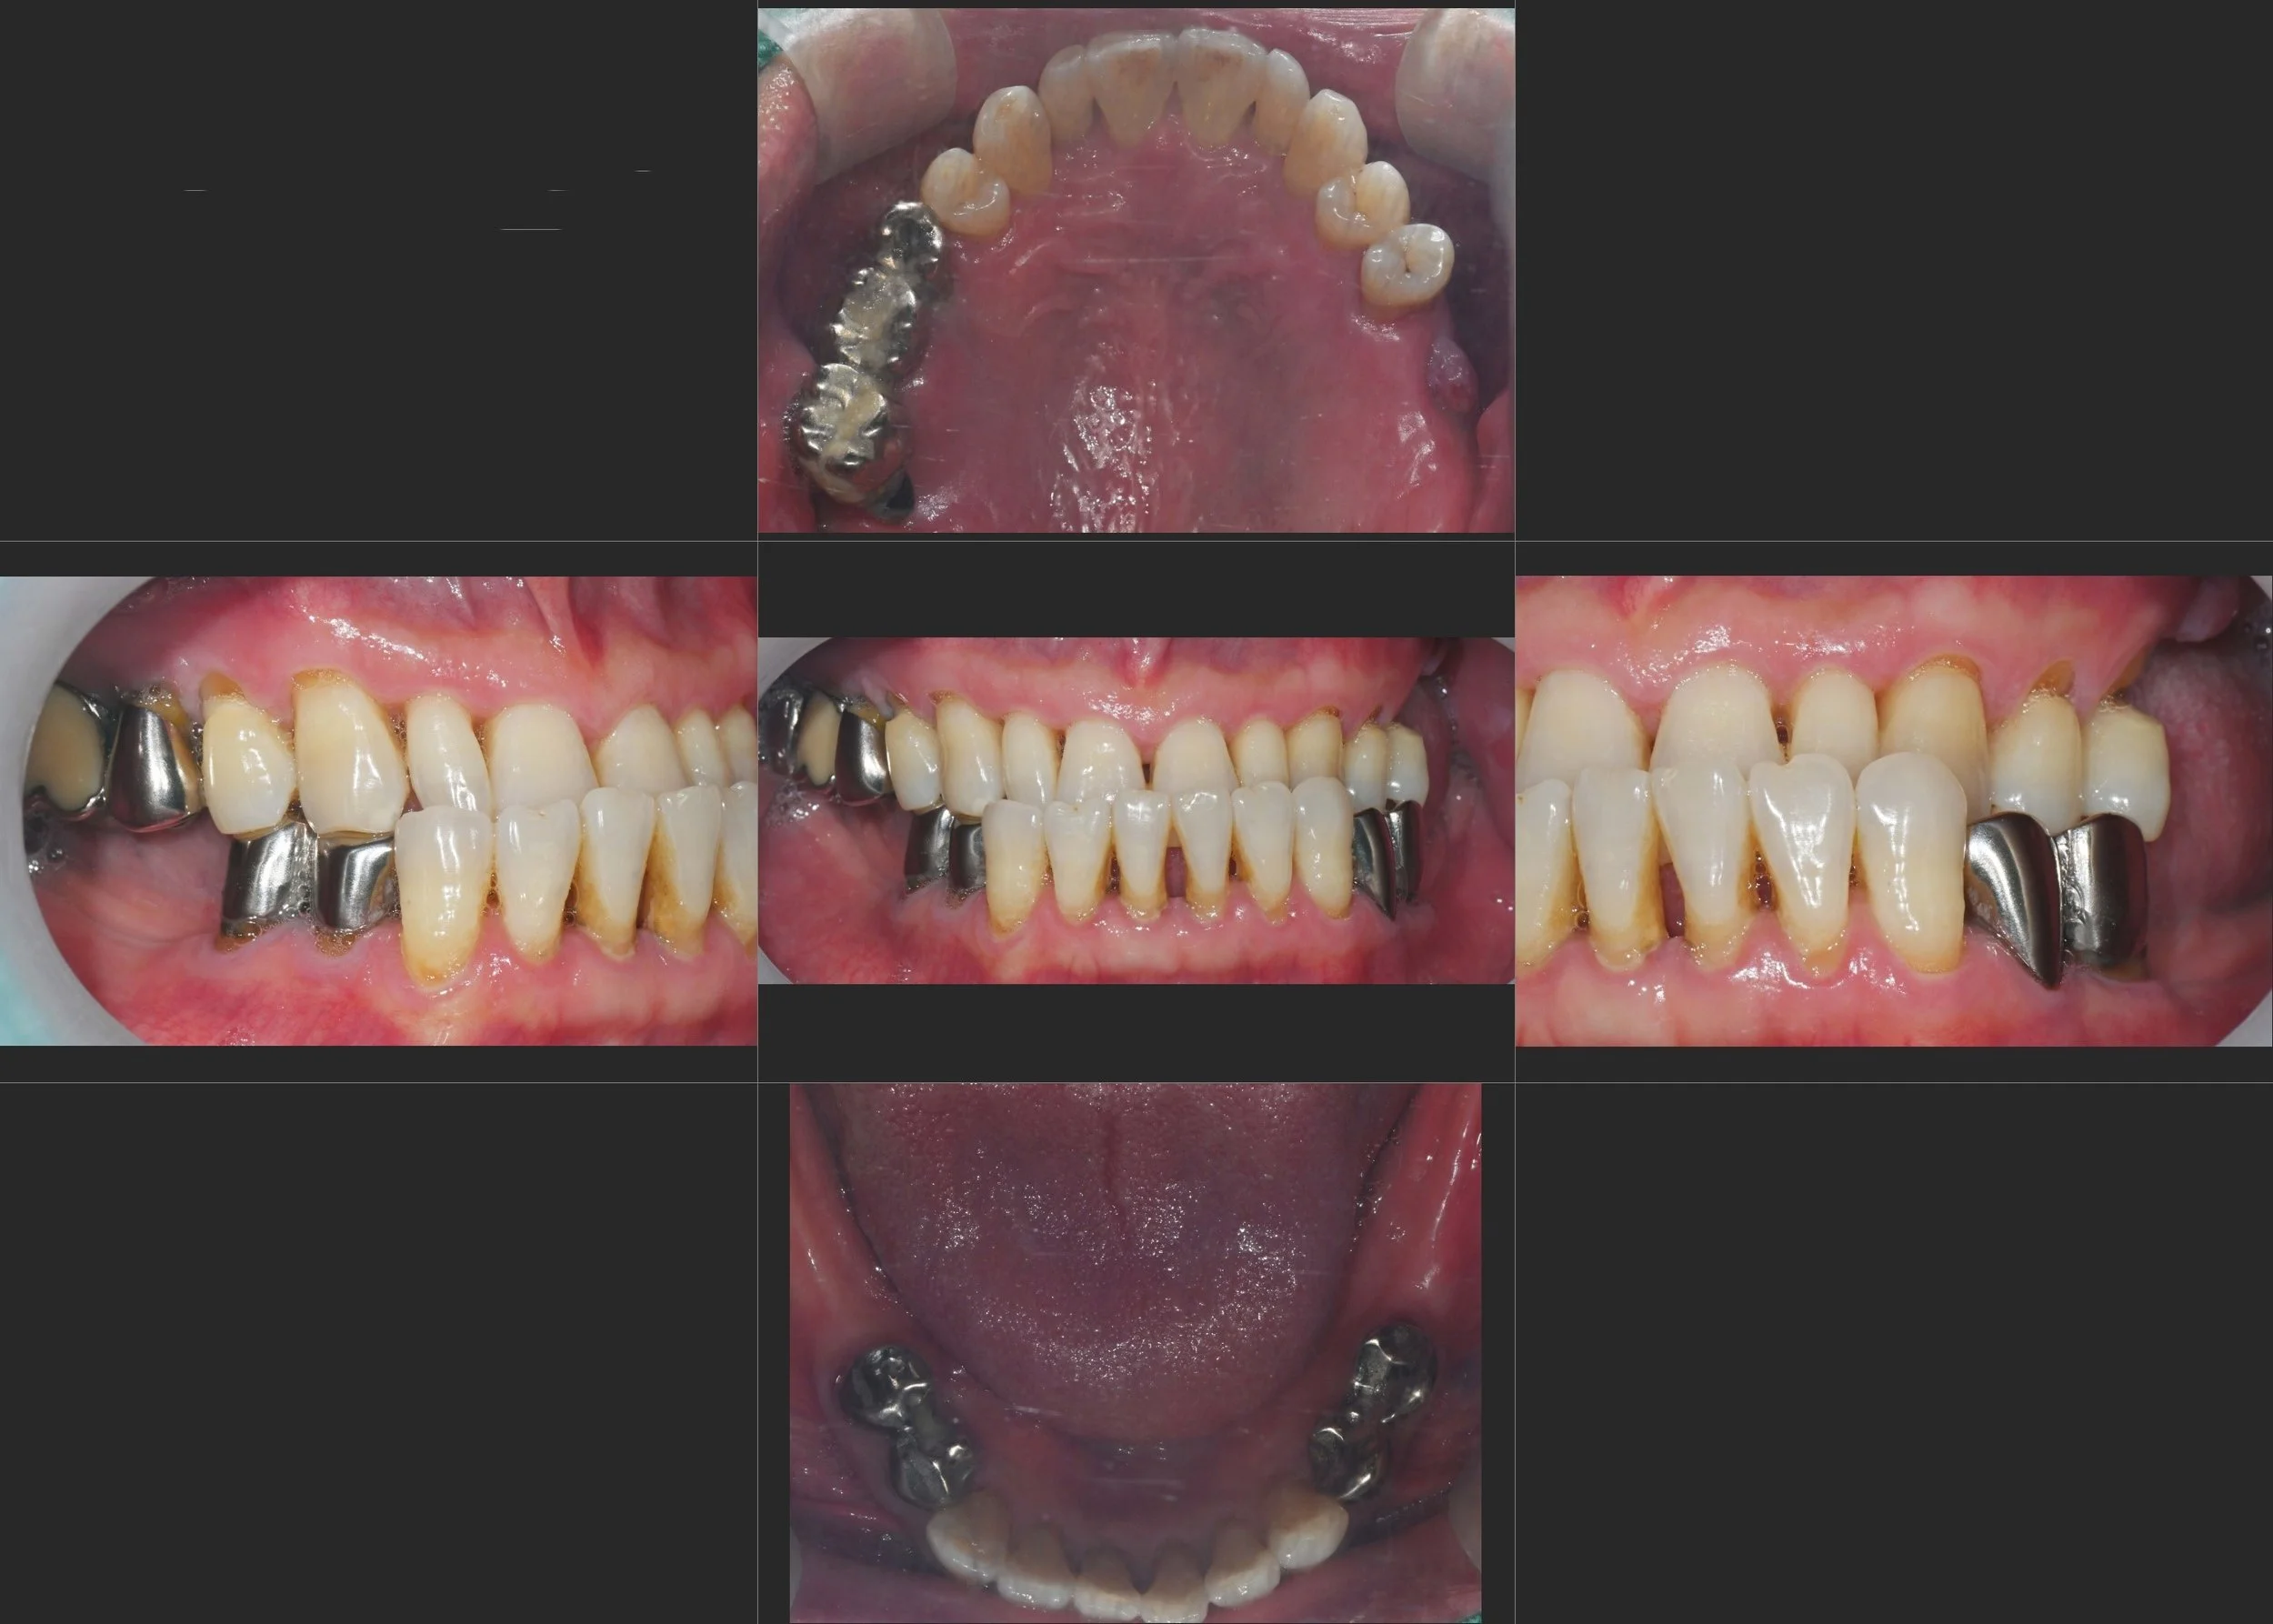

38. Comprehensive Full-Arch Reconstruction: Reversing the Domino Effect of Tooth Loss

Management of Generalized Severe Periodontitis and Posterior Bite Collapse in a Female Patient in her 60s. A Systematic Approach to VDO Recovery and Strategic Esthetic Rejuvenation.